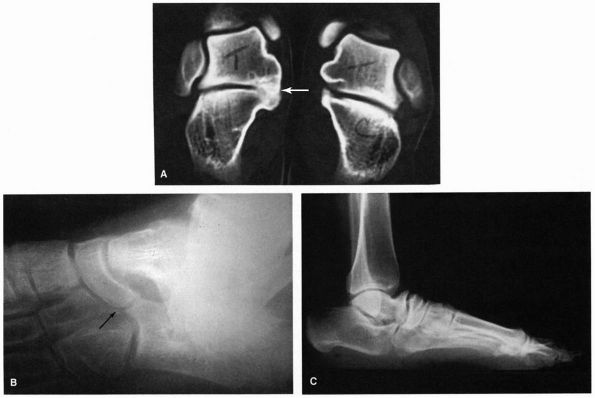

|

FIGURE 21-22. Tarsal coalitions. (A) Talocalcaneal middle facet coalition (arrow). (B) Calcaneonavicular coalition. (C)

Changes secondary to a tarsal coalition consist of beaking and irregularity of the talonavicular joint, abnormal appearance of the subtalar joint, and lack of dorsiflexion pitch to the calcaneus. |